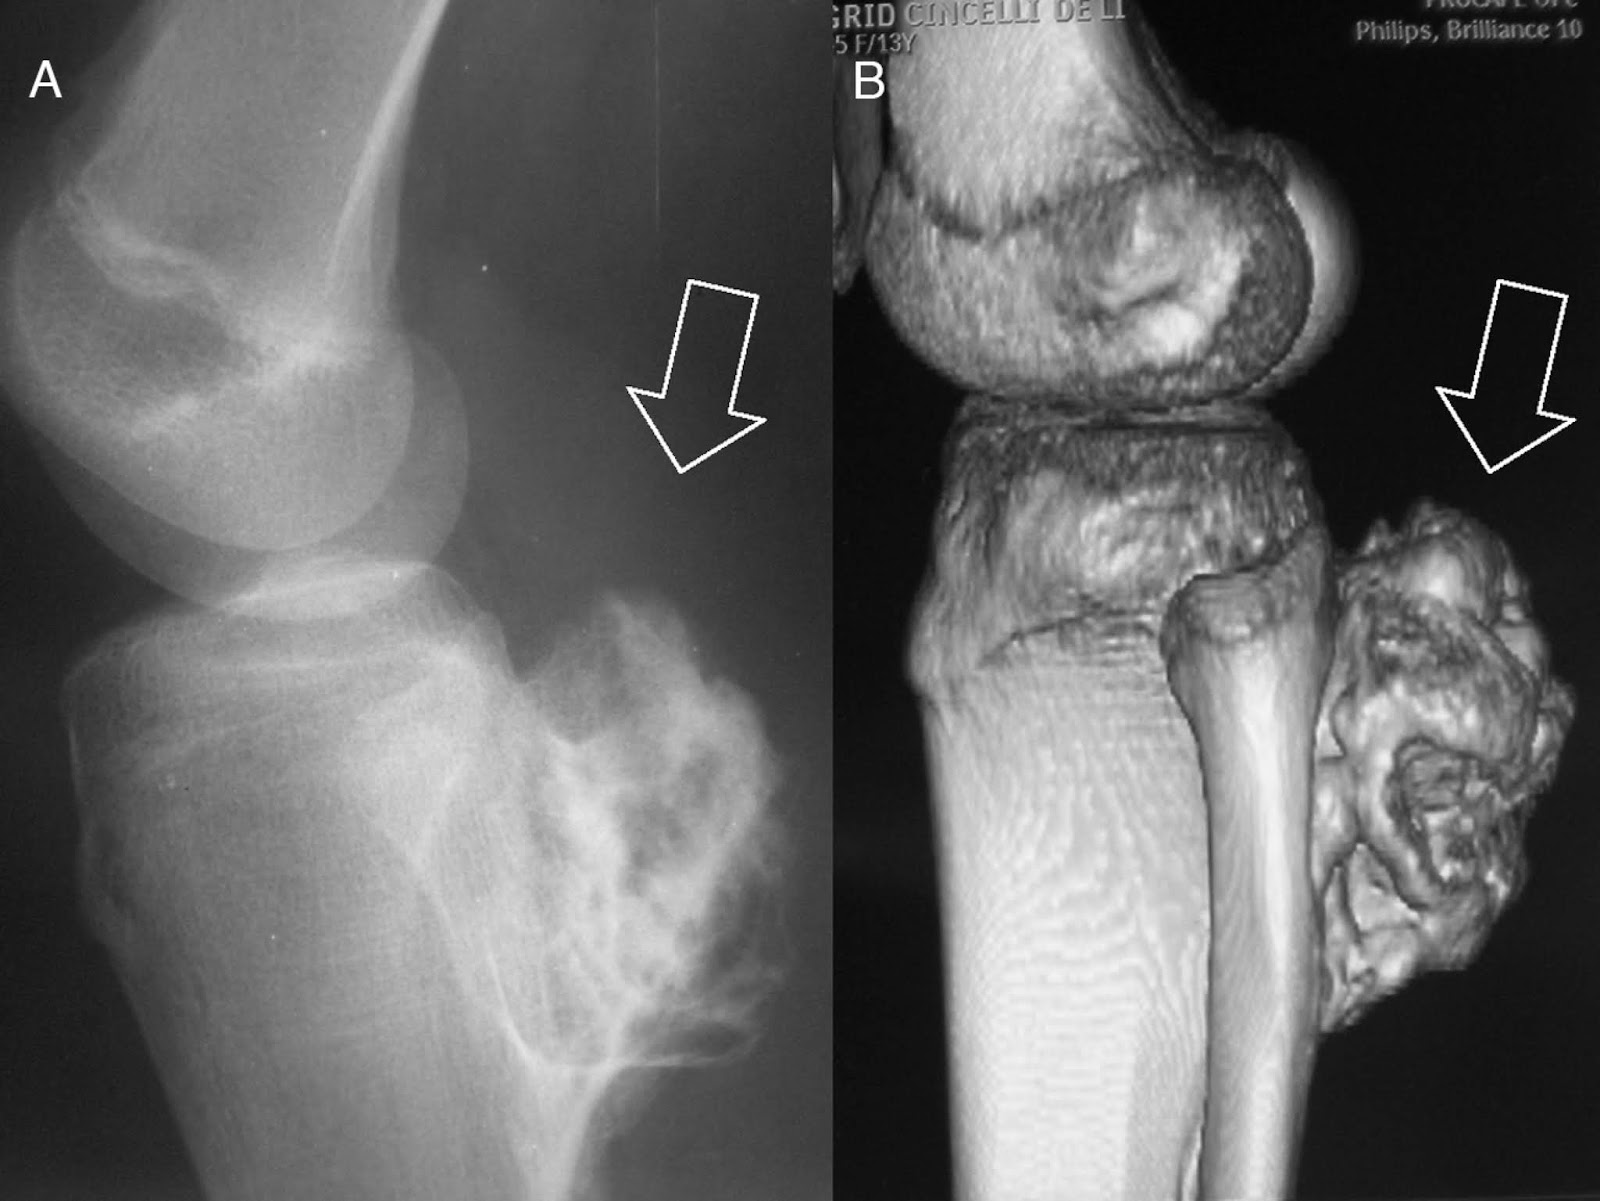

A resposta para essa pergunta é não. Embora o tumor ósseo seja mais raro ele ainda existe e atinge anualmente cerca de 2.700 pessoas, o crescimento de um tumor pode substituir o tecido saudável dos ossos por um anormal, o qual irá enfraquecer a estrutura óssea podendo provocar fraturas e lesões facilmente, formando assim um “caroço” ou nódulo.Ele pode ocorrer em qualquer osso do sistema esquelético de um ser humano, porém os mais comuns são os longos dos braços e coxas, coluna e pelve. Ele pode ser divido em dois, tumor ósseo primário que é quando o câncer atinge diretamente os ossos e tumor osso secundário ou metastático, onde ele começa em algum órgão e vai para os ossos, além disso, pode ser dividido em benigno quando é facilmente curado e não se propaga pelo corpo, e maligno que é grave e necessita de tratamento especifico que irá variar de acordo com a origem do tumor e as lesões causadas, o tratamento pode ser através de radioterapia, quimioterapia, cirurgia e em alguns casos o paciente pode receber uma prótese ou um osso doador, correndo risco de vida.

- Osteossarcoma: afeta mais jovem do sexo masculino.

Imagem disponível em:< http://romariorochaortopedista.com.br/tumores/tumor-osseo/ >. Acesso em: 20 mai. 2019